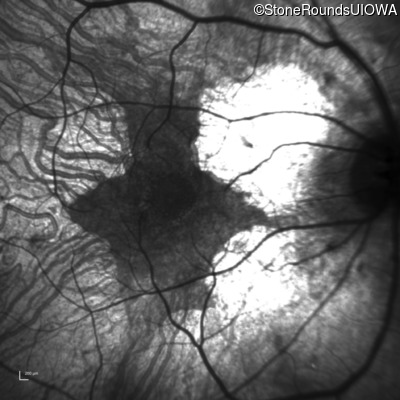

Infrared Fundus Photograph - Left - 20/12.5 -2

Exemplar